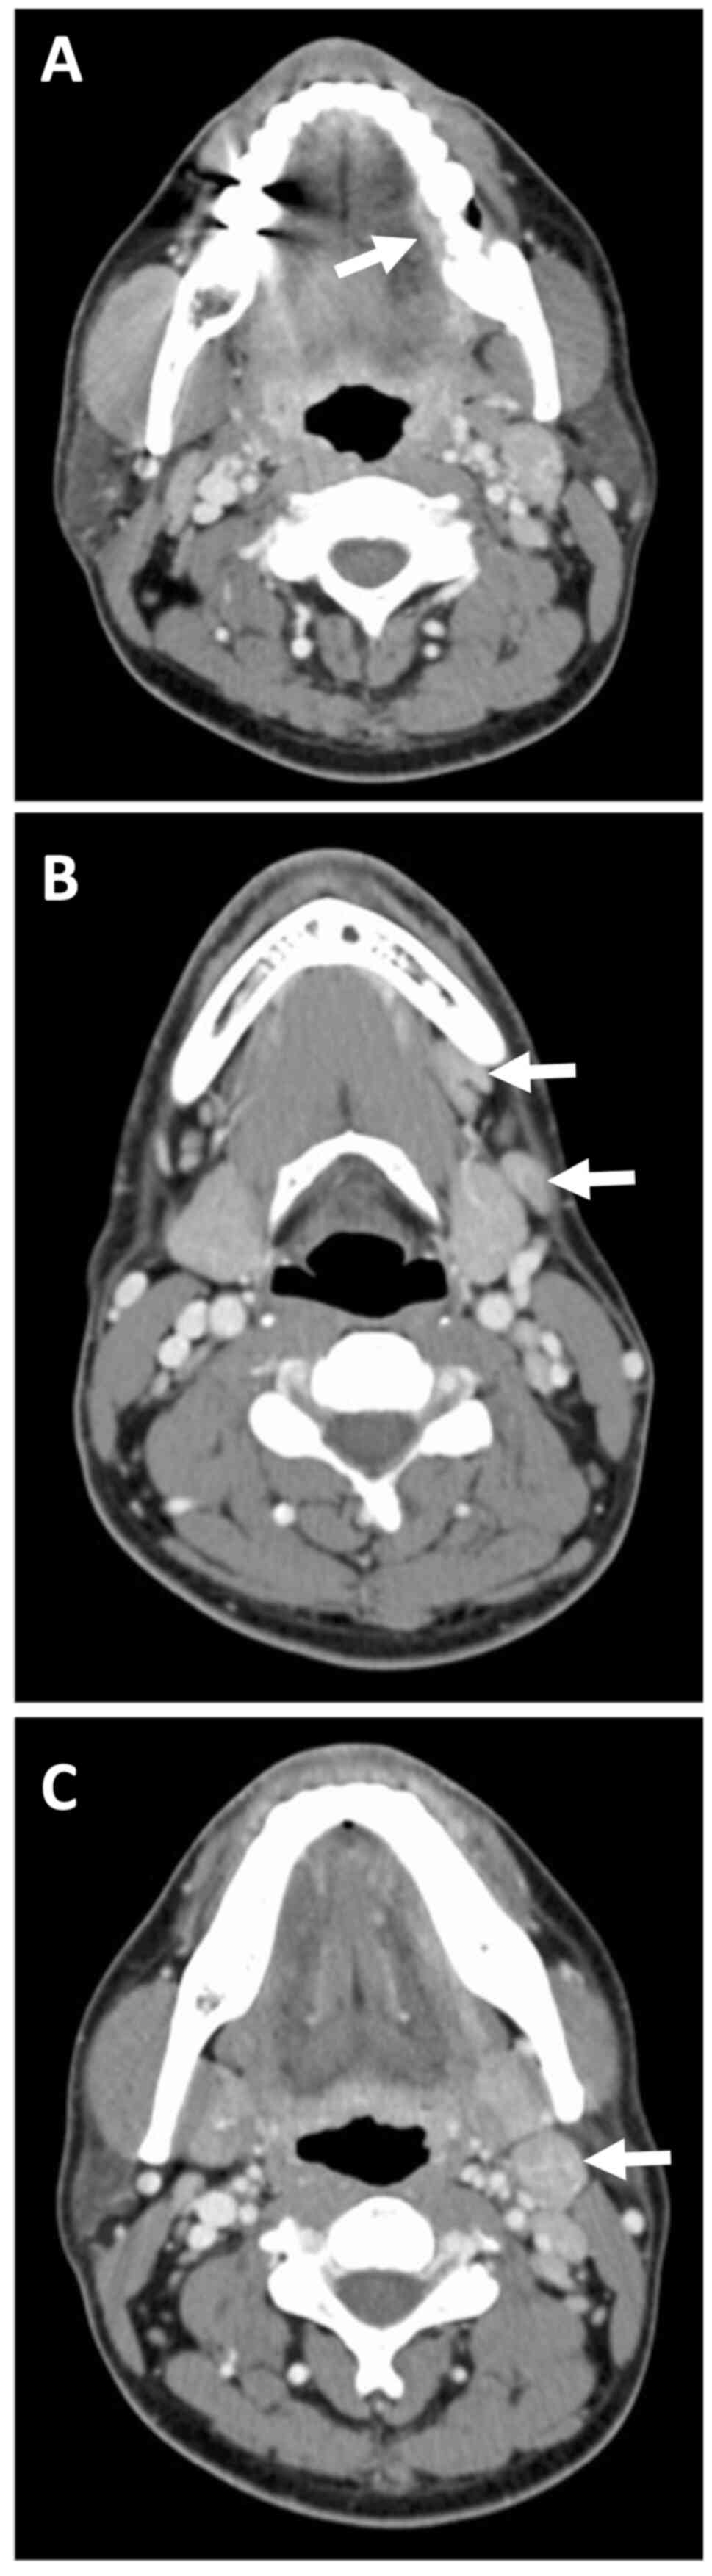

Contrast-enhanced computed tomography (CT) confirmed a shallow enhancing lesion in the left tongue, and the left submandibular and upper internal jugular lymph nodes were also enlarged (Fig. 2A-C). Blood tests revealed mild leukocytosis (WBC: 10,500/µl) with 75% neutrophils and a slight increase in C-reactive protein (CRP: 0.6 mg/dl). Liver and renal function tests were within normal limits. A biopsy of the tongue ulcer was performed, and histopathological examination revealed typical features of HSV infection, including multinucleation, molding of nuclear contours, and intranuclear inclusions, which were positive for HSV1 by immunohistochemistry (Fig. 3A and B). Serological testing showed elevated HSV IgM levels and low HSV IgG levels, suggesting primary HSV infection. The patient's clinical symptoms subsided within 1 week without antiviral treatment, and a follow-up examination demonstrated increasing HSV IgG titers.

Figure 2.

Contrast-enhanced computed tomography images. (A) Arrow indicates a shallow enhancing lesion in the left lateral border of the tongue. (B) Arrows point to an enlarged left submandibular lymph node. (C) Arrow shows an enlarged left upper internal jugular lymph node.